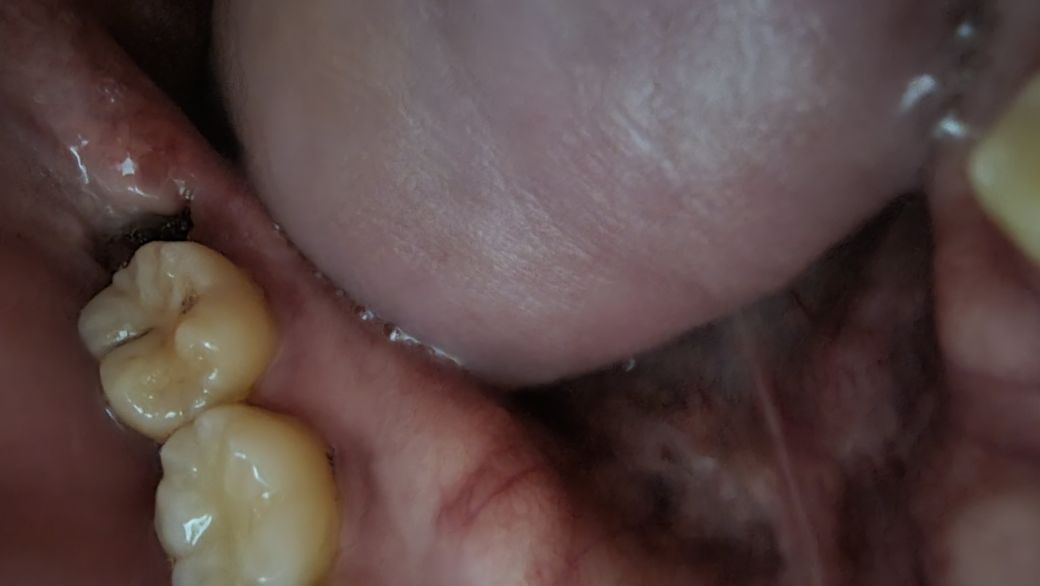

사랑니 발치 5일차에 혈병이 떨어졌는데 괜찮은건가요?

이번주 수요일에 오른쪽 아래 부분매복사랑니를 잇몸절개 없이 발치했고 소독은 금요일에 받았습니다.

오늘 아침에 핸드폰 라이트로 비춰서 거울로 보니 혈병 상부가 반쯤 탈락하여 발치한 부위의 절반만 혈병이 차있습니다.

이물감은 있으나 통증은 전혀 없는데 드라이소켓에 걸릴까 걱정됩니다.

• 1번 째 사진

사진으로 보아 문제가 있는 것은 아닙니다. 수요일 발치후 혈병이 일부 떨어져 나가는 것은 정상적인 치유과정입니다.

현재 통증이 없다면, 사진상으로 드라이소켓이 올것같진 않습니다. 사진은 정상적인 치유과정을 보여주고 있습니다.